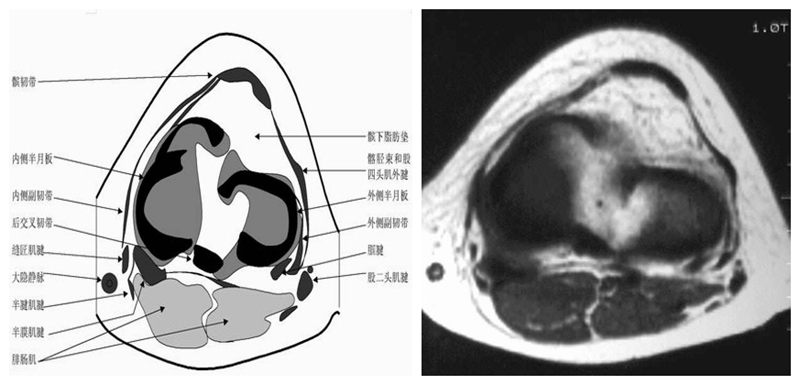

膝关节横断面MRI解剖

三维影像首选的方位,便于与CT比较,可准确地展现髌骨内外侧关节面。

横断面解剖第二层